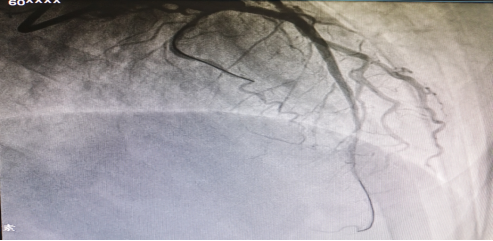

【前降支闭塞开通后造影】

2022年3月初,60岁的聂叔叔,因“阵发性胸闷胸痛1月,加重3天入院”,住院期间行冠脉造影检查示左前降支主支自开口完全闭塞,TIMI血流0级。经过我科介入团队通力合作,历时2小时成功开通患者前降支闭塞病变。术后胸闷痛症状明显缓解,日前已顺利出院,生活质量较前提高。